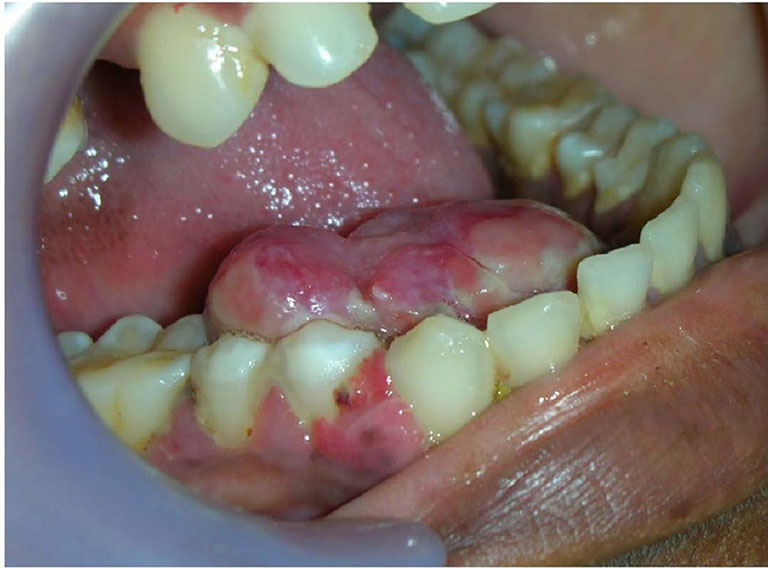

- Giai đoạn u xương hàm gây biến dạng xương: Ở giai đoạn này u sẽ làm phồng bề mặt xương, làm bệnh nhân có cảm giác nặng vùng xương hàm hoặc mất cảm giác do thần kinh bị chèn ép.

- Giai đoạn u hàm mặt phá vỡ bề mặt xương: Có thể sờ thấy khối u nhưng không đau, bờ xương xung quanh mỏng, bén nhọn.

- Giai đoạn u xương hàm tạo đường rò và gây biến chứng: Lỗ rò sẽ làm thủng ở mặt trong hoặc ngoài miệng, để lại nhiều di chứng khó hồi phục.

Nếu khối u là ác tính, u lớn lên sẽ gây ra áp lực bên trong hàm, ép lên răng, dây thần kinh, mạch máu và xương hàm. Các triệu chứng như đau hàm, sưng mặt và răng lung lay dễ rụng sẽ rõ rệt hơn ở giai đoạn sau của bệnh.